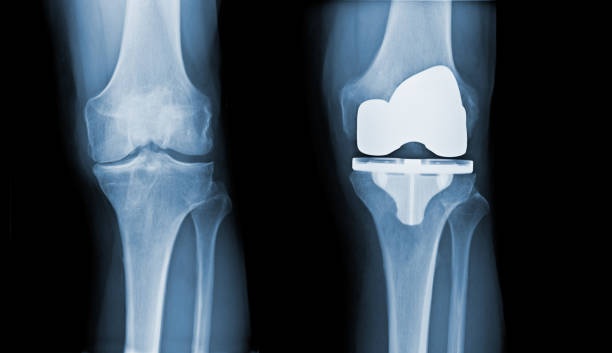

Total knee replacement surgery, also known as total knee arthroplasty or TKR/TKA, is a surgical marvel that involves replacing a damaged or deteriorated knee joint with an artificial joint or prosthesis. Typically, this surgery is recommended for individuals grappling with debilitating knee pain due to conditions such as osteoarthritis, rheumatoid arthritis, or traumatic injuries to the knee joint. So, how do you know if a knee replacement is the right course of action for you? Orthopedic surgeons often suggest that when the time is right for a replacement, you'll instinctively know it. Before jumping to the surgical option, most orthopedists advocate exploring physical therapy as an initial measure to see if surgery can be avoided. If a total knee replacement is still the recommended course of action even after pursuing physical therapy, take comfort in the knowledge that your dedication to PT has not been in vain. Research reveals that individuals who undergo pre-surgery physical therapy tend to achieve more favorable post-operative results!

- The artificial knee joint, consisting of metal and plastic components, is securely implanted. The femoral component replaces the end of the thigh bone, the tibial component replaces the top of the shinbone, and a plastic spacer is inserted between them to allow smooth movement.

- If needed, the undersurface of the kneecap (patella) may be resurfaced with a plastic component.